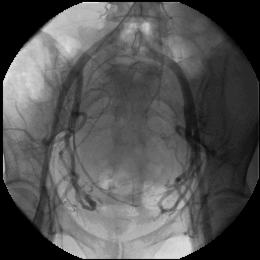

Bei der interventionellen Therapie erfolgt durch Embolisation (Einschwemmung von kleinen Kunstpartikeln) die Verödung von Myomen. Dazu wird nach örtlicher Betäubung durch einen Radiologen ein Katheter in die Leistenarterie eingebracht, über den winzige Kügelchen in das Myom eingeschwemmt werden, die dafür sorgen, das die Blutzufuhr zum Myom unterbunden wird. Innerhalb von drei bis sechs Monaten schrumpfen die Myome bis auf ca. die Hälfte ihrer Ausgangsgröße. Diese Methode kann also vorteilhaft für Frauen sein, deren Familienplanung zwar abgeschlossen ist, die aber einen Organerhalt wünschen.